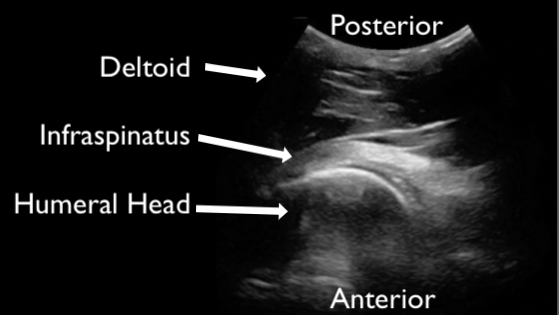

Figure 1 demonstrates normal appearing layers of soft tissue, fascia, muscle and bone. In general, the epidermis, fascia, and bone are hyperechoic compared to subcutaneous fat and muscle (which are hypoechoic). Bone will typically produce a clean shadow. Figure 2 demonstrates normal bony cortex in a long axis with shadow below. Muscle in a short axis is mostly hypoechoic with a few hyperechoic portions (Figure 3). In the long axis you can appreciate muscle fiber striations (Figure 4). Tendon in a long axis appears as a thin, well demarcated structure with striated fibers (Figure 5). Figure 6 demonstrates the principle of anisotropy, which is most apparent when imaging tendons and muscles. Muscle and tendon may appear focally hypoechoic depending on the angle of the transducer, but this is artefactual and will disappear with further interrogation. Figure 7 demonstrates a normal shoulder joint with no anechoic effusion and normal articulation of the glenoid and the humeral head.

Figure 7. An example of a normal joint. This still image of the shoulder demonstrated deltoid, humeral head articulating with glenoid, and the infraspinatus tendon. The image is acquired from the posterior shoulder.